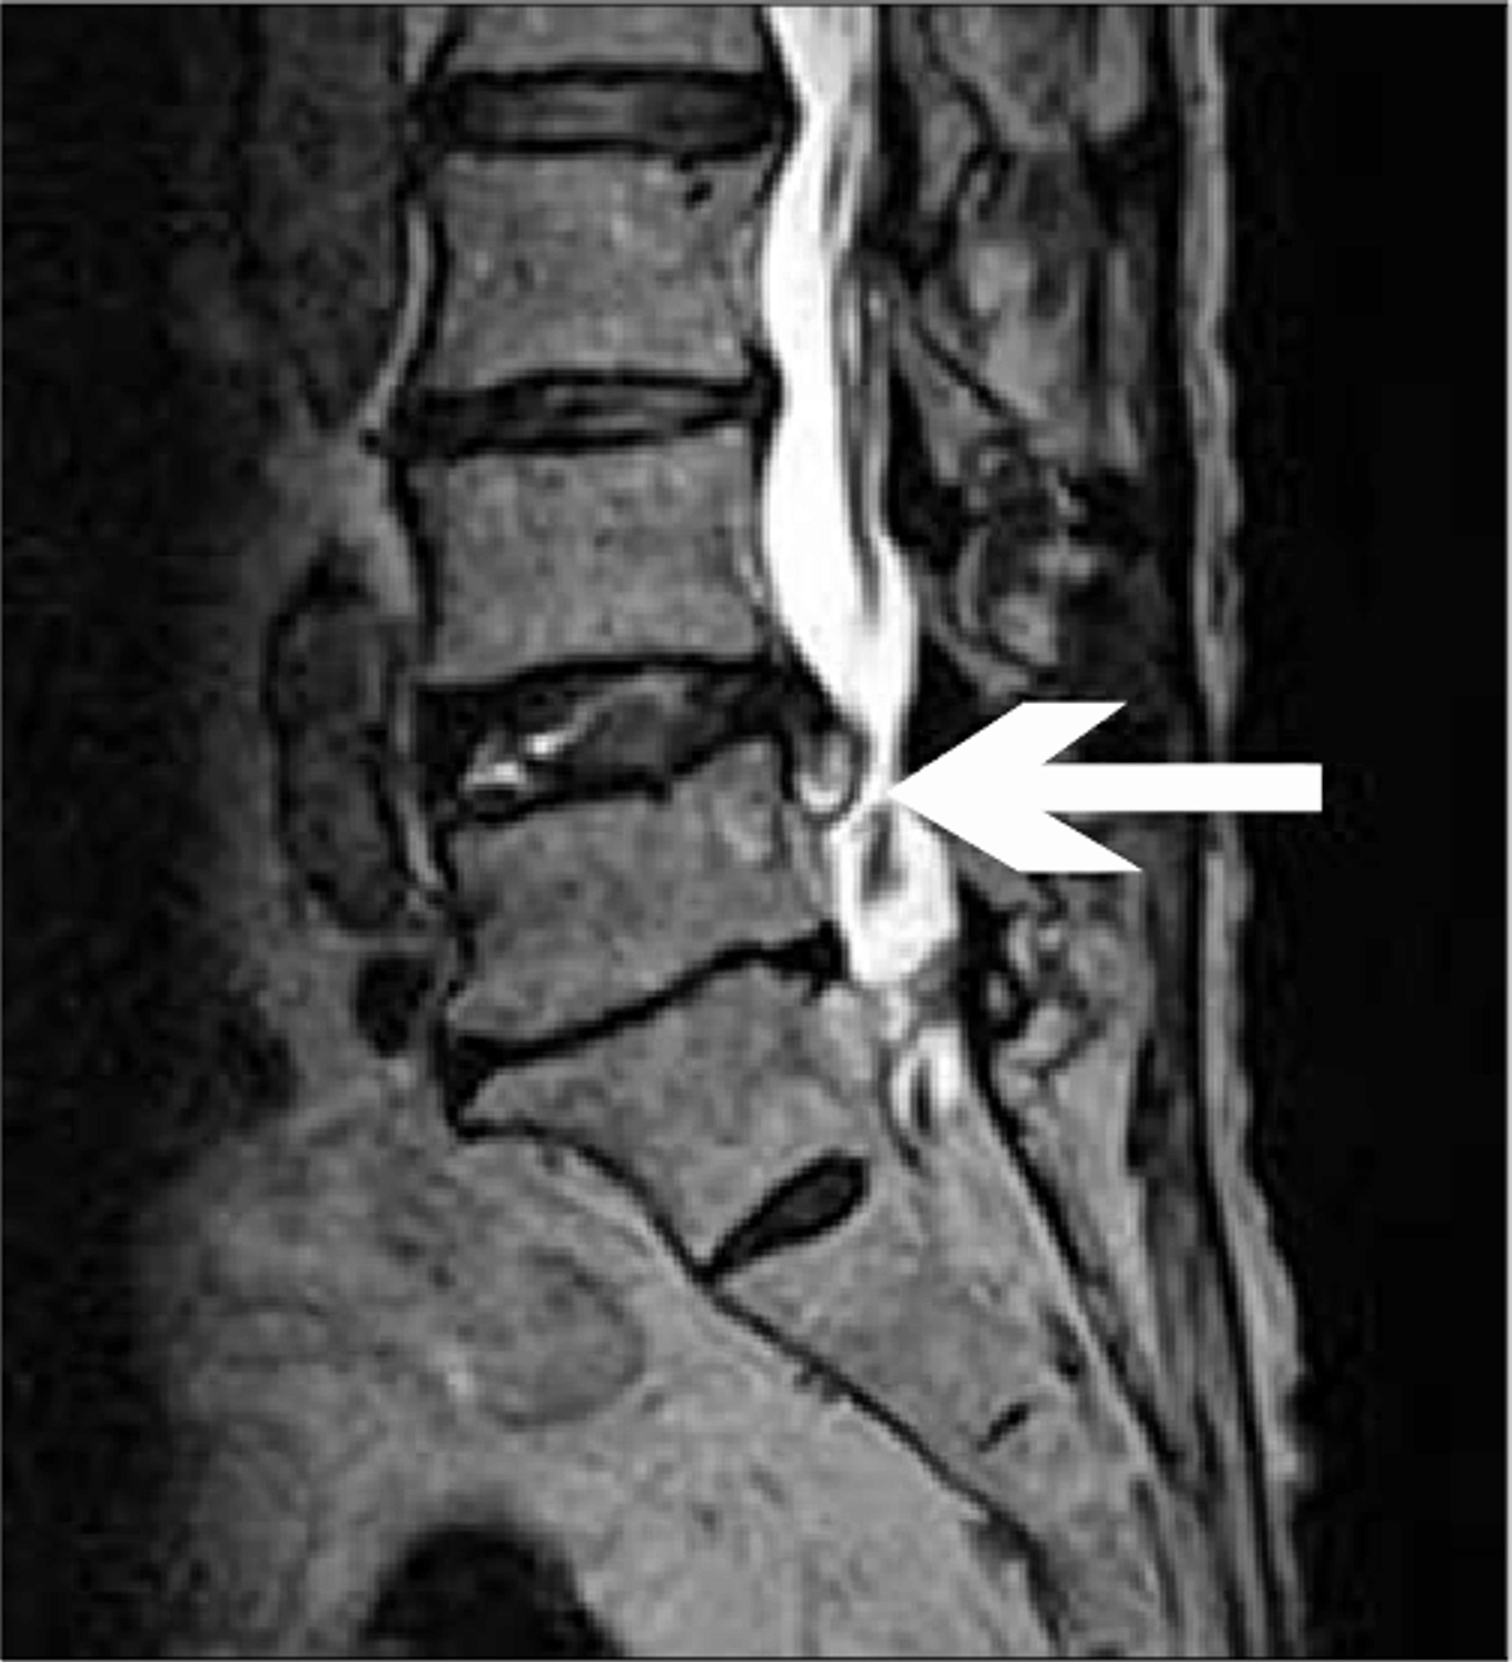

Question 2/2 - The patient undergoes an MRI as below identifying a paracentral herniated intervertebral disk.

Based on the patient history and radiology findings, which spinal nerve is most likely affected?